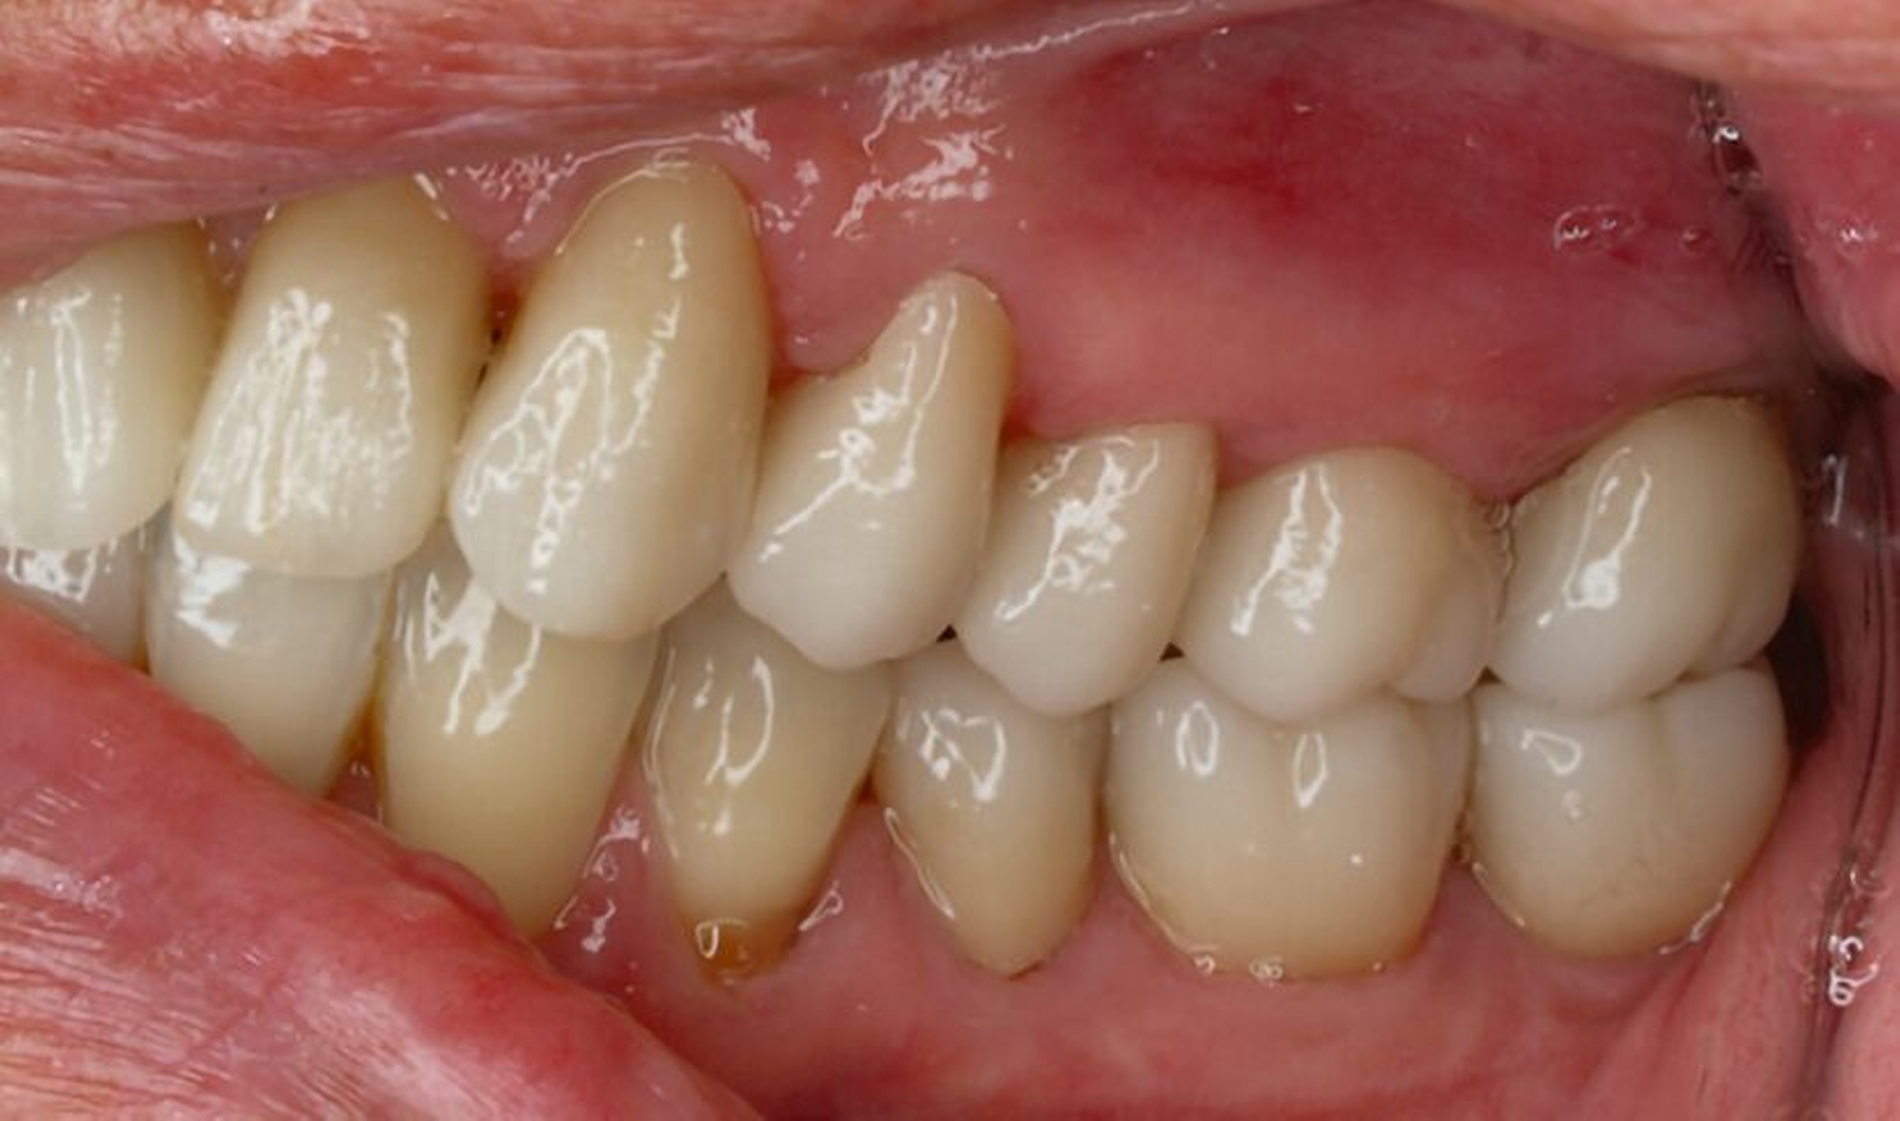

Tabelle 1 zeigt das entsprechende Befundschema mit den Taschentiefen mesial und distal, den Lockerungsgraden und den Sensibilitätsüberprüfungen mittels Kältespray (ViPr). Die Ruheschwebelage wurde mithilfe des Zielinsky-Zirkels auf 2 mm bestimmt. Die Nonokklusion im Seitenzahnbereich konnte auf circa 1,5 mm bemessen werden. Tabelle 2 spiegelt das entsprechende Okklusionsprotokoll wider. Das Okklusionsprofil wird auch in den Abbildungen 3a bis 3c deutlich.

Die anschließenden Verlaufskontrollen zeigten klinisch stabile Verhältnisse. Der prothetische Behandlungsaufwand betrug etwa acht Monate inklusive Planung, Begutachtung, Durchführung und Inkorporation des Zahnersatzes. In den Folgeterminen wurde der Patientin noch eine Aufbissschiene für den Unterkiefer eingegliedert, um Schäden durch etwaigen Schlafbruxismus vorzubeugen [Macedo et al., 2007]. Für die Nachsorge empfiehlt sich ein halbjährliches Kontrollintervall. Die erfolgte Okklusionskorrektur im Seitenzahnbereich wird in Abbildung 11 deutlich.